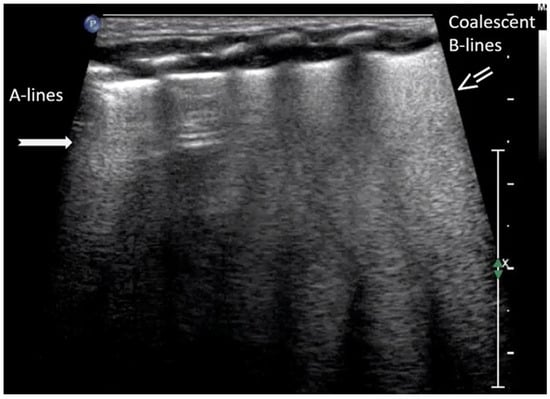

B-lines are vertical reverberation-like hyperechoic artifacts seen during LUS imaging which originate from the pleural line and extend to the bottom of the imaging field without fading in intensity (Figure 2a). B-line artifacts move in synchrony with lung sliding and intersect horizontal A-lines, effectively obscuring them. Their presence is typically associated with fluid accumulation in the alveoli or interstitial space, and they are commonly referred to as ultrasound lung comets. However, B-lines are frequently observed in neonates and can appear as a normal finding within the first 24 to 48 h after birth [13,14,17]. During LUS imaging, identification of up to two B-lines at the lung base is considered to be normal, while the presence of three or more B-lines between the intercostal space in a single view is considered significant and indicative of an underlying pathology. If multiple B-lines are identified by LUS, then the patient likely suffers from interstitial syndrome. When the air content in the lungs decreases, the number of lines tends to increase, because of the associated increase in lung density. Moreover, when the identified B-lines are confluent, this is an indication that the alveoli are filled with sub-pleural fluid. When interstitial edema is present, the presence or absence of B-lines can guide the administration of fluids [16,17,18,19]. However, it should be noted that B-lines are absent in the aforementioned pneumothorax.

B-lines: Vertical reverberation-like hyperechoic artifacts originate from the pleural line and extend to the bottom of the image (a). This artifact could be normal (<3 in an intercostal space) or abnormal when are more than three, multiple or coalescent B-lines (b).

According to severity of the lung or interstitial pathology, B-lines may be solitary, few, multiple or even coalescent (Figure 2b), resulting in three imaging patterns associated with increasing severity: black lung, black and white lung, or white lung (Figure 3) [20,21].

RDS is a common cause of neonatal respiratory failure, particularly in preterm infants, resulting from surfactant deficiency and alveolar collapse. LUS has become a valuable diagnostic tool for RDS, offering real-time visualization of lung pathology at the bedside [38,42,43,44,45]. A hallmark sonographic feature of RDS is the presence of dense, confluent B-lines throughout the lung fields, producing a “white lung” appearance due to the loss of normal aeration. Notably, the whole lung is typically involved, with a diffuse, bilateral distribution that distinguishes RDS from more localized pulmonary conditions [37,46,47]. Additionally, interspersed consolidations may be present, including hypoechoic and subpleural areas of alveolar collapse, reflecting regions of complete de-aeration. These consolidations often lack air bronchograms and are associated with irregular or thickened pleural lines. The combination of diffuse B-line patterns, global lung involvement, and patchy consolidations provides a highly suggestive ultrasound profile of RDS and facilitates early diagnosis. In addition, for RDS, LUS may be used for severity assessment and the monitoring of treatment response in the neonatal intensive care setting [16,20,27,29]. The ability of the LUS to characterize the severity of the RDS is debatable (Figure 14 and Figure 16) [48].